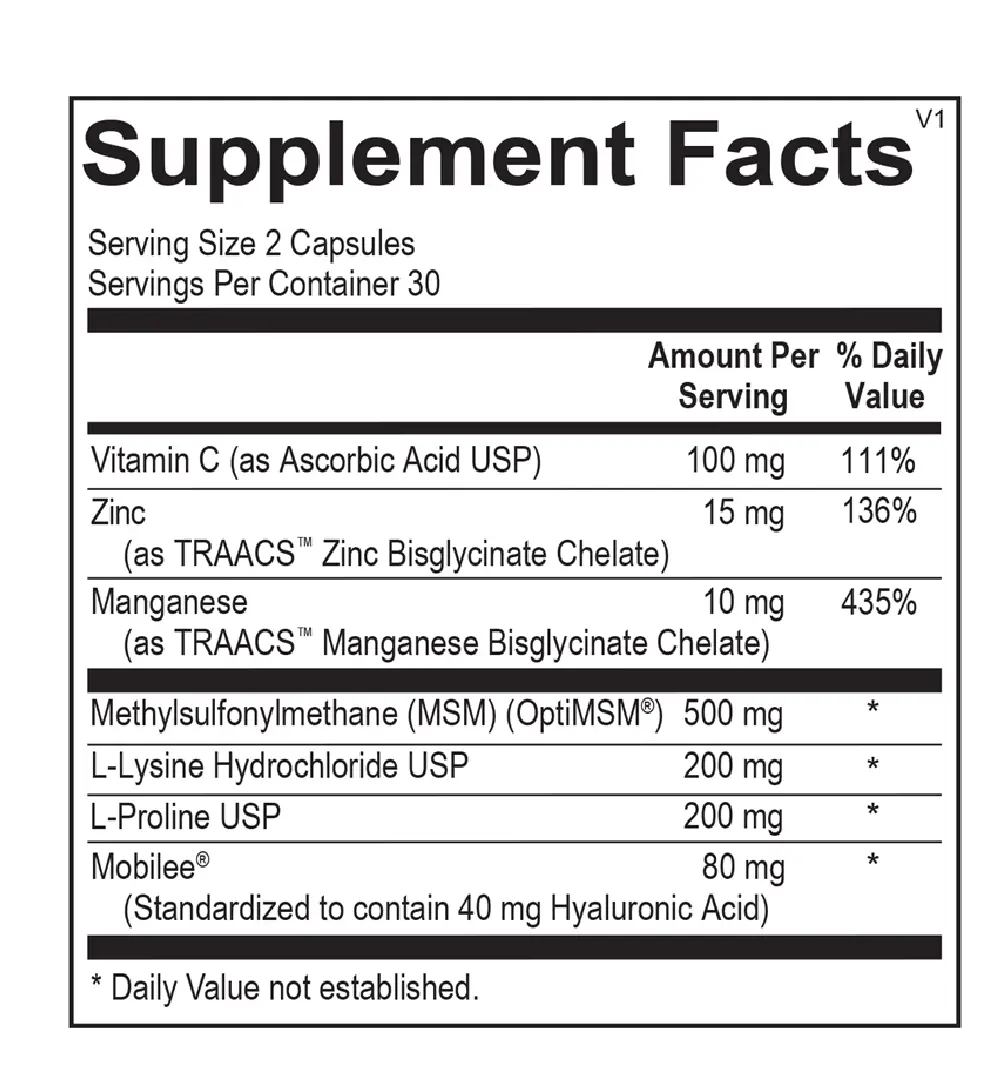

Provides essential amino acids and minerals to promote comfort and flexibility.

Aids in restoring joint and tendon resilience, complementing exercise and GLP-1 wellness programs.